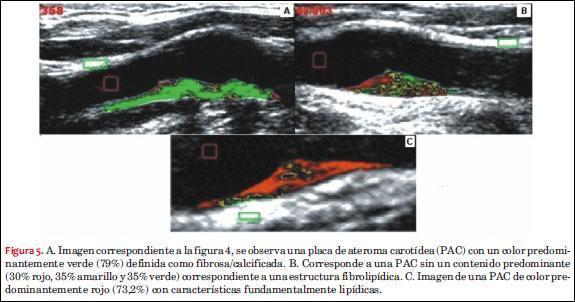

Composición y clasificación de la PAC

En aquellos individuos en los cuales se identificó PAC, se determinó su composición estructural a partir del análisis de los niveles de grises de la imagen ecográfica seleccionada, como se representa en las figuras 4 y 5. La resolución cuenta con 256 niveles de gris (0 = negro; 255 = blanco). El procedimiento de procesamiento de la imagen consiste en desplazar dos volúmenes de muestra, uno rojo y otro verde, dentro del lumen arterial hipoecoico (“referencia sangre”) y otra sobre la pared de la arteria hiperecoica, (“referencia adventicia”), respectivamente (figura 4). Este procedimiento de normalización permite compensar la ganancia del ecógrafo y las diferencias propias de estructura del paciente(32). Mediante la determinación manual a partir de clics de un área de interés, el operador delimita la PAC creando un polígono que la encierra dentro de un contorno. El número de pixeles dentro del contorno se utiliza para estimar el tamaño de la PAC en ese corte ecográfico. El tamaño de cada pixel se aproxima utilizando la calibración del ecógrafo, que resulta para el nivel de magnificación habitual entre 102 y 140 pixeles/cm. A cada pixel de la placa se le asigna un valor (“nivel de gris”) de acuerdo a su ubicación en la escala de grises. Se modifica la imagen a una normalizada según su composición, determinando la MNG de acuerdo a la intensidad global de los pixeles de la PAC(12,13,32).

Con la imagen normalizada de la escala de grises, el software realiza automáticamente un mapeo en tres colores (rojo, amarillo y verde), dependiendo de su valor de la escala de niveles de grises. Los puntos de corte para el rojo, amarillo y verde fueron <50, entre 50-80 y >80, respectivamente(29). Este método determina “áreas rojas” dentro de la PAC, correlacionadas con un contenido hemorrágico o lipídico (ecogenicidad similar a la sangre); “áreas verdes”, correspondientes a una ecogenicidad similar a la adventicia representando contenido fibroso o calcificado; mientras que “áreas amarillas” abarcan el conjunto intermedio de la escala de grises entre las dos anteriores, que representan sectores con contenido fibrolipídico(13).

La clasificación de las PAC según su composición en tres grupos (hipoecogénica = lipídica; = isoecogénica = fibrolipídica; hiperecogénica = fibro/calcificada) se basa en la clasificación propuesta por Polak y colaboradores(53) y fue realizada automáticamente por el software y validada por los operadores. Se definió una PAC como fibrosa/calcificada (FC) o lipídica (L) cuando su estructura se componía de más de 50% por áreas hiperecoicas (“áreas verdes”) o menos de 50% por áreas hipoecoicas (“áreas rojas”), respectivamente. A su vez, se definió como placa fibrolipídica (FL) cuando ninguno de los componentes de las escalas de grises superó el 50%. En la figura 5 se puede observar un ejemplo de cada tipo de PAC a partir del mapeo de colores aportado por el software. Todas las imágenes fueron calibradas de manera protocolizada y estandarizada para permitir la comparación entre las PAC y reducir al mínimo las diferencias metodológicas.